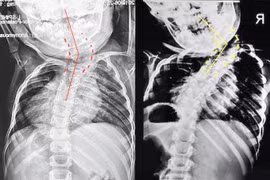

(khoahocdoisong.vn) - Lần đầu tiên Bệnh viện Đa khoa Phú Thọ đã phẫu thuật thành công chỉnh hình cột sống cho trẻ bị vẹo cột sống nặng > 45 độ. Đây là một kĩ thuật phức tạp, thường được triển khai ở bệnh viện tuyến trung ương. Phẫu thuật sớm không chỉ giúp trẻ lấy lại vóc dáng mà còn tránh các biến chứng nguy hiểm về chức năng hô hấp, tim mạch...

(khoahocdoisong.vn) - Biến dạng cột sống rất nặng và cứng nên bắt buộc phải phẫu thuật 2 đường. Phẫu thuật giúp chỉnh cong vẹo, trẻ cao thêm được 11-13cm. Hãy nhận biết các dấu hiệu trẻ bị biến dạng cột sống để cho trẻ đi khám sớm.